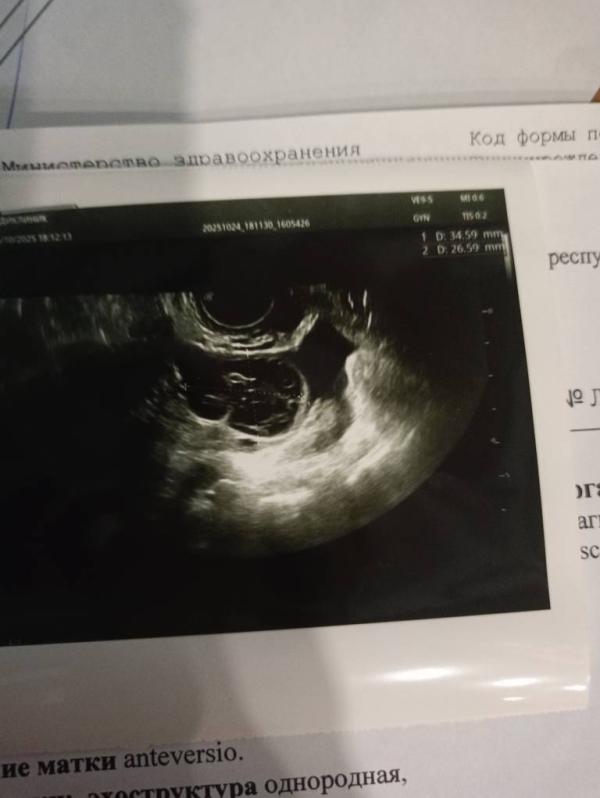

На данный момент 15 день цикла, тесты на овуляцию отрицательные. Самочувствие в норме. В анамнезе киста правого яичника и воспаление в омт.